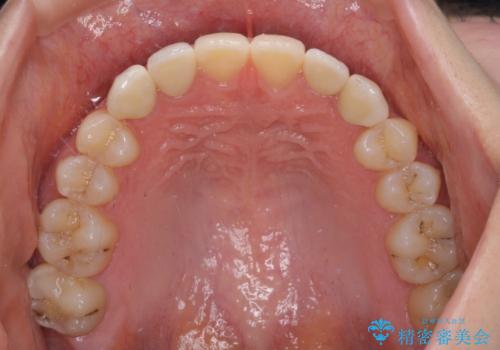

- 前歯の奇形や欠損、乳歯残存などによる審美障害を気にして来院された患者様です。

正中の隙間は矯正治療により閉じ、左右の4歯はオールセラミッククラウンにて補綴することとしました。

前歯2本もセラミッククラウンを装着することで隙間を閉じる治療方法もあるかと思いますが、健全な歯を削る必要は全くなく、矯正治療で対応することが望ましい治療であると考えます。